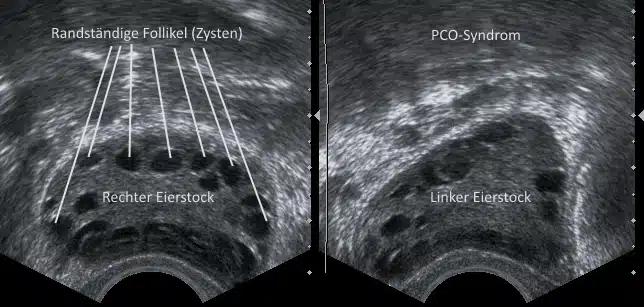

- Ultraschalluntersuchung: Mittels Ultraschall können die Eierstöcke und die Anzahl der Zysten beurteilt werden.